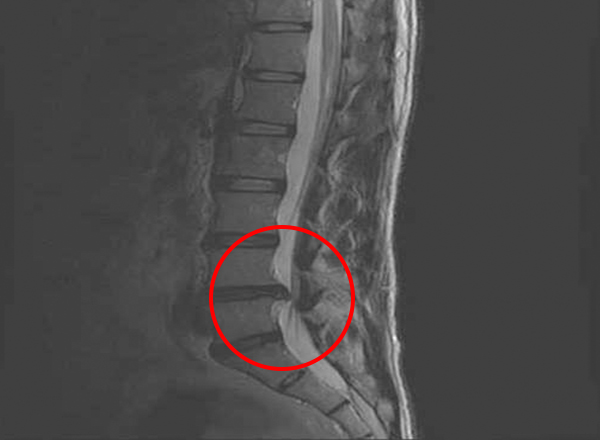

└ 지금 내 통증이 단순 근육통인지, 디스크 위험 단계인지 1~5단계 체크리스트로 구분합니다. - 2편. 허리디스크 수술 전 MRI 판독법, 초보자 가이드

└ L4-L5, L5-S1 같은 용어와 ‘돌출·탈출·신경 압박’ 표현을 쉽게 풀어서 설명합니다. - 3편. 허리디스크 수술비·보험·지원금 실전 정리